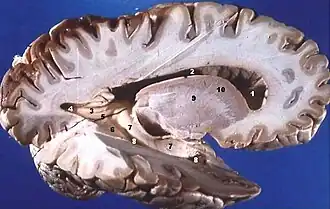

Grey matter is distributed at the surface of the cerebral hemispheres (cerebral cortex) and of the cerebellum (cerebellar cortex), as well as in the depths of the cerebrum (the thalamus; hypothalamus; subthalamus, basal gangliaputamen, globus pallidus and nucleus accumbens; as well as the septal nuclei), cerebellum (deep cerebellar nuclei – the dentate nuclei, globose nucleus, emboliform nucleus, and fastigial nucleus), and brainstem (the substantia nigra, red nucleus, olivary nuclei, and cranial nerve nuclei).